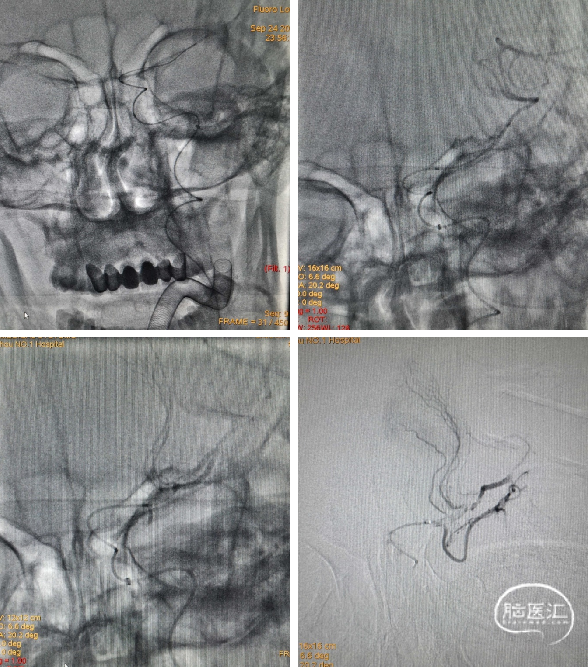

术后2月来院复查造影:左侧颈内动脉起始部狭窄严重,左侧大脑中动脉M1段血流通畅。予以植入颈动脉支架。